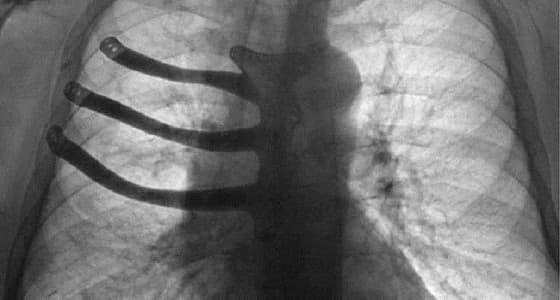

استطاع عدد من الأطباء بمدينة سوانسي، في بريطانيا، للمرة الأولى من نوعها، طباعة جزء مستأصل من القفص الصدري لمريض يبلغ من العمر 71 عامًا، وذلك باستخدام طابعة ثلاثية الأبعاد " 3D " .

حيث قام الأطباء، باستئصال نصف عظم القص، وثلاثة أضلاع من القفص الصدري للمريض الذي يدعى " بيتر ماغزو " ، وذلك بعد إصابته بورم سرطاني.

حيث سمحت لهم الطابعة " ثلاثية الأبعاد " ، بطبع الأجزاء المستأصلة من سبيكة تيتانيوم، وتقليص فترة العملية إلى ساعتين، فيما تم استخدام التصوير المقطعي للقفص الصدري للمريض، أثناء عملية طبع هذه الأجزاء.

جدير بالذكر، أن هذه هي أول عملية طبع تتم لمثل هذه الأجزاء في بريطانيا، حيث أكد الأطباء، أنهم سوف يستخدمون هذه الطريقة مستقبلًا بعد نجاحها، فيما استغرقت العملية الجراحية للاستئصال مدة 8 ساعات، ونجحت تمامًا، طبقًا لما ذكره الأطباء الذين قاموا بها.